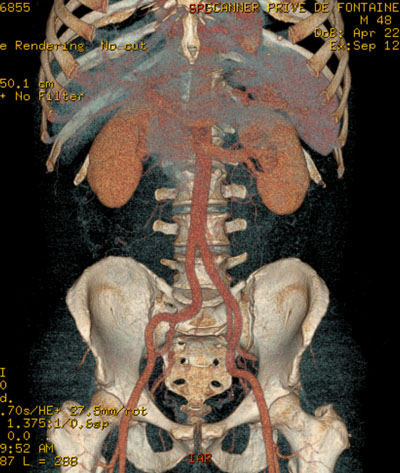

Angioscanner

C’est une technique particulière du scanner pour explorer les vaisseaux de l’organisme (artères et veines). C’est la technique de référence, après le Doppler, pour rechercher des rétrécissements (sténoses) ou des dilatations (anévrysme) des artères. Elle nécessite l’utilisation systématique d’un produit de contraste.